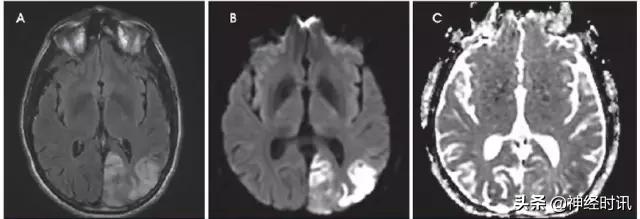

肝性脑病

轻型肝性脑病的典型影像学表现为对称性苍白球T1低信号。严重病例的MRI显示皮层(特别是扣带回和岛叶)和基底节T2高信号和弥散受限(图9)。丘脑、脑室旁白质和脑干也可能受累。弥散性皮质受累是可逆的,但永久性神经功能后遗症的风险会上升。ADC值降低可能是由于血氨导致的兴奋毒性损伤和星形胶质细胞渗透压异常。

图9 一例53岁女性,酒精性肝硬化,因腹痛、恶心和呕血就诊于急诊。数天后,她出现无反应,伴脑干反射消失,血*水氨**平达360。她被诊断为肝性脑病,MRI显示双侧额叶和岛叶皮层和丘脑轻度弥散受限(A:DWI,B:ADC)和FLAIR高信号(C)。豆状核有轻度T1高信号(D)。